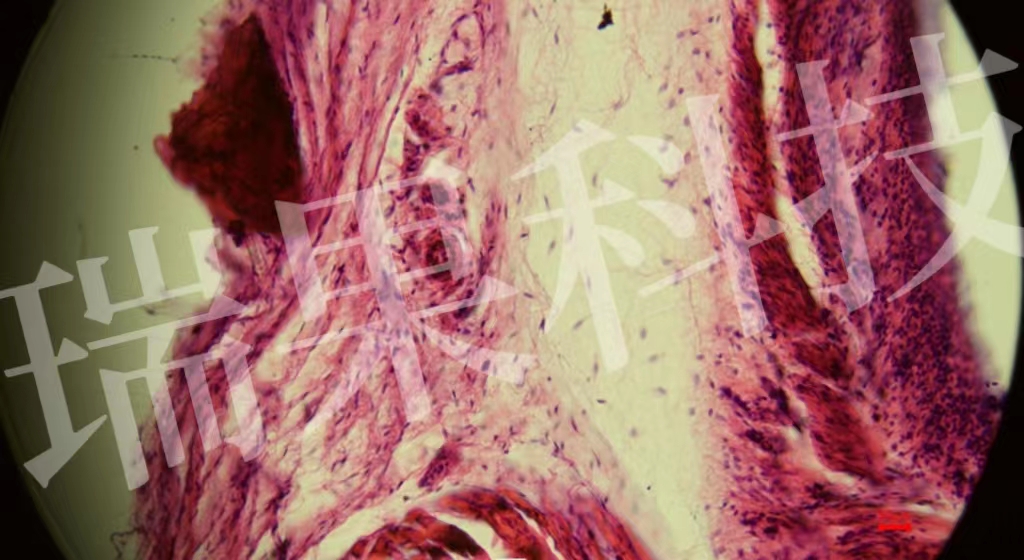

HE染色:苏木精 - 伊红染色法 ( hematoxylin-eosin staining ) ,简称HE染色法 ,石蜡切片技术里常用的染色法之一 。苏木精染液为碱性 ,主要使细胞核内的染色质与胞质内的核酸着紫蓝色 ;伊红为酸性染料 ,主要使细

HE染色:苏木精 - 伊红染色法 ( hematoxylin-eosin staining ) ,简称HE染色法 ,石蜡切片技术里常用的染色法之一 。染液为碱性 ,主要使细胞核内的染色质与胞质内的核酸着紫蓝色 ;伊红为酸性染料 ,主要使细胞质和中的成分着红色 。HE染色法是组织学、、病理学教学与科研中最基本、使用最广泛的技术方法。

心1-1-20x